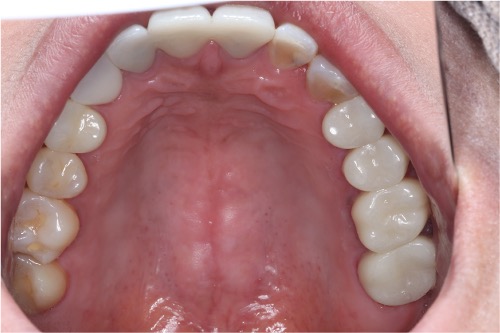

症例①

年齢40代女性

治療期間1ヶ月

治療内容セラミック治療、インプラント治療、ホワイトニング

治療箇所セラミック:左上1番、2番 左下5番、7番 右上1番、2番、3番、4番、5番 右下5番、6番、7番

インプラント:左下6番

治療費用500,000円

インプラント治療、セラミック治療

ホワイトニング